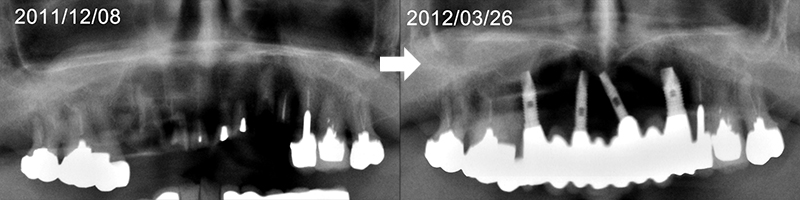

現在80歳を超えた方々が60歳半ば以降70歳代半ばころまでに、ご自身の歯を思い切ってオーバーホールした後の10年以上の経過を供覧いたします。

下顎に広範囲のインプラント治療が施され快適に過ごされていたので、上顎前方部の歯質劣化により残存歯でのブリッジが不能のためインプラント修復をご希望

義歯を使われることなく12年使用され、90歳手前で急に衰えられご逝去されました。